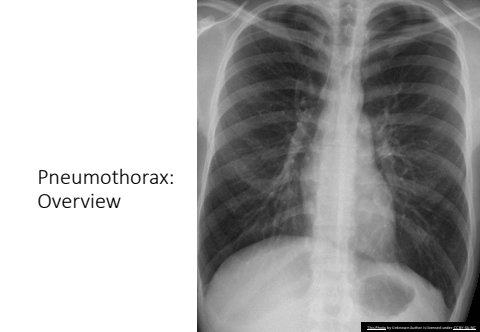

Pneumothorax: OverviewThis Photo by Unknown Author is licensed under CC BY-SA-NC